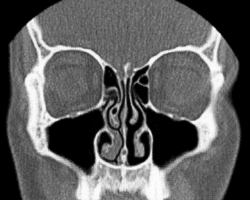

Le cycle nasal est l'alternance inconsciente d'une congestion (ou gonflement) et d'une décongestion (ou dégonflement) partielles des fosses nasales chez l'homme et d'autres animaux[1],[2],[3],[4]. Il en résulte un débit d'air plus important dans une narine avec une alternance périodique entre les narines. Il s'agit d'une congestion physiologique des cornets nasaux due à l'activation sélective d'une moitié du système nerveux autonome par l'hypothalamus. Elle ne doit pas être confondue avec l'obstruction nasale.

Il a été démontré que les cils du côté congestionné suspendent leur motilité jusqu’à ce que ce côté se décongestionne. Ainsi, le cycle garantit qu'un côté du nez est toujours humide ce qui facilite l'humidification, qui est l'une des trois fonctions du nez, les deux autres étant la filtration et le réchauffement de l'air inspiré avant son entrée dans les poumons[6].